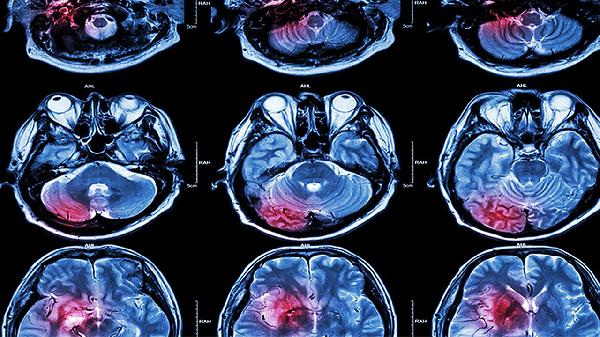

脑溢血伴随烟雾病是可以治疗的,但治疗方案需根据病情严重程度和个体差异制定。脑溢血是指脑内血管破裂导致的出血,而烟雾病是一种慢性脑血管疾病,表现为颅内小血管网状扩张,形似烟雾。